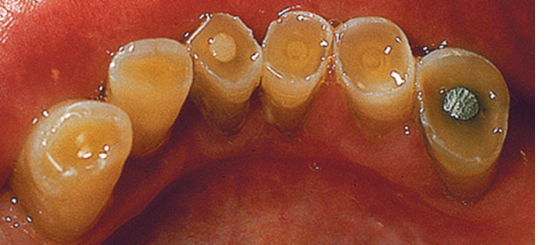

<p>1. After reviewing Fig. 5.23, what term would you use to describe this wear?</p><p>a. Abfraction</p><p>b. Abrasion</p><p>c. Attrition</p><p>d. Erosion</p>

1. After reviewing Fig. 5.23, what term would you use to describe this wear?

d. Erosion

2. Using the Universal Numbering System what tooth numbers are wearing in Fig. 5.23?

a. 8, 9

<p>6. What tooth tissue is seen in Fig. 5.23 that is yellow in color?</p><p>a. Enamel</p><p>b. Dentin</p><p>c. Cementum</p><p>d. Pulp</p>

6. What tooth tissue is seen in Fig. 5.23 that is yellow in color?

b. Dentin

<p>9. Looking at Fig. 5.23, which tooth/teeth looks suspicious on the mesial surface using the International Numbering System?</p><p>a. 1.2</p><p>b. 1.3</p><p>c. 2.3</p><p>d. b. and c.</p>

9. Looking at Fig. 5.23, which tooth/teeth looks suspicious on the mesial surface using the International Numbering System?

a. 1.2